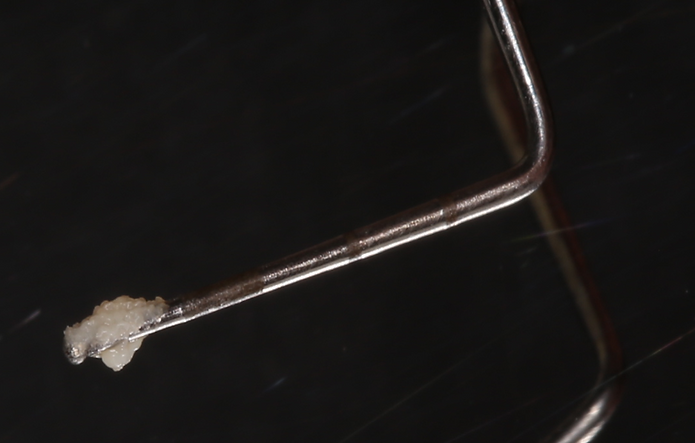

Bakteryjna płytka nazębna, która tworzy się na powierzchniach zębów oraz uzupełnieniach protetycznych (ruchomych czy stałych) jest uważana za najważniejszy czynnik miejscowy, który powoduje zapalanie dziąseł . Płytka nazębna umiejscawia się w okolicy szyjki zęba i w przestrzeniach między zębami/ koronami/implantami.

W pierwszym momencie jest miękka i łatwa do usunięcia za pomocą odpowiedniej techniki i przyborów do higieny.

Natomiast już po około 3 dniach zaczyna mineralizować w kamień nazębny, który staje się niemożliwy do usunięcia codziennymi zabiegami pielęgnacyjnymi.